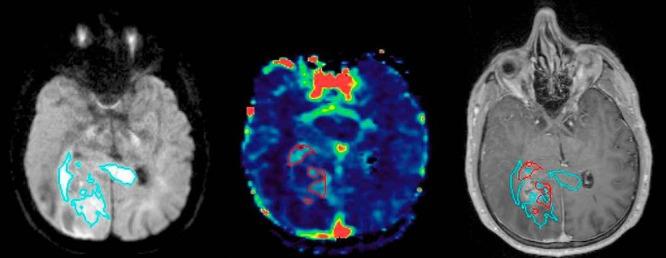

Quantitative mapping of hyperperfused and hypercellular regions of glioblastoma has been proposed to improve definition of tumor regions at risk for local recurrence following conventional radiation therapy. As the processing of the multiparametric dynamic contrast-enhanced (DCE-) and diffusion-weighted (DW-) magnetic resonance imaging (MRI) data for delineation of these subvolumes requires additional steps that go beyond the standard practices of target definition, we sought to devise a workflow to support the timely planning and treatment of patients. A phase II study implementing a multiparametric imaging biomarker for tumor hyperperfusion and hypercellularity consisting of DCE-MRI and high b-value DW-MRI to guide intensified (75 Gy/30 fractions) radiation therapy (RT) in patients with newly diagnosed glioblastoma was launched. In this report, the workflow and the initial imaging outcomes of the first 12 patients are described. Among all the first 12 patients, treatment was initiated within 6 weeks of surgery and within 2 weeks of simulation. On average, the combined hypercellular volume and high cerebral blood volume/tumor perfusion volume were 1.8 times smaller than the T1 gadolinium abnormality and 10 times smaller than the FLAIR abnormality. Hypercellular volume and high cerebral blood volume/tumor perfusion volume each identified largely distinct regions and showed 57% overlap with the enhancing abnormality, and minimal-to-no extension outside of the FLAIR. These results show the feasibility of implementing a workflow for multiparametric magnetic resonance-guided radiation therapy into clinical trials with a coordinated multidisciplinary team, and the unique and complementary tumor subregions identified by the combination of high b-value DW-MRI and DCE-MRI.

已有人提出对胶质母细胞瘤的高灌注和高细胞区域进行定量映射,以更好地界定常规放射治疗后有局部复发风险的肿瘤区域。由于处理多参数动态对比增强(DCE-)和扩散加权(DW-)磁共振成像(MRI)数据以描绘这些子体积需要超出靶区定义标准做法的额外步骤,我们试图设计一种工作流程以支持患者的及时规划和治疗。开展了一项II期研究,该研究采用由DCE-MRI和高b值DW-MRI组成的用于肿瘤高灌注和高细胞性的多参数成像生物标志物,以指导新诊断胶质母细胞瘤患者的强化(75 Gy/30次分割)放射治疗(RT)。在本报告中,描述了前12例患者的工作流程和初始成像结果。在前12例患者中,均在手术6周内且模拟2周内开始治疗。平均而言,高细胞体积与高脑血容量/肿瘤灌注体积之和比T1钆异常小1.8倍,比液体衰减反转恢复(FLAIR)异常小10倍。高细胞体积和高脑血容量/肿瘤灌注体积各自识别出的区域在很大程度上不同,与强化异常区域有57%的重叠,且在FLAIR之外的延伸最小至无延伸。这些结果表明,在多学科团队协作下,将多参数磁共振引导放射治疗工作流程应用于临床试验是可行的,并且高b值DW-MRI和DCE-MRI联合识别出了独特且互补的肿瘤子区域。